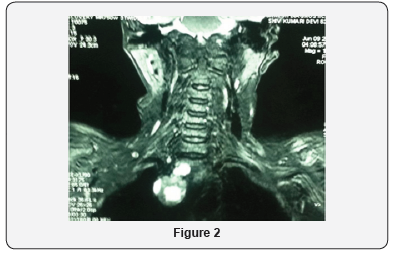

On radiological evaluation, her DEXA scan showed T score of -3.0 at the region of distal radius bone. Her ultrasound whole abdomen revealed non-obstructing 2mm stone right renal upper calyx. Ultrasound neck showed no abnormality. Sestimibitechnetium 99m scan revealed uptake over right mediastinal region (Figure 1). MRI neck and chest revealed 2.5cmx2.0cm oval shaped hyperintense lesion in the right paratracheal region in postero superior mediastinum (Figure 2). With the diagnosis of primary hyperparathyroidism with ectopic mediastinal parathyroid adenoma, she was optimized for surgery. She underwent Video- assisted thoracoscopic surgical approach.3 ports were made. 2 working ports of 5mm size were made on right anterior axillary and midclavicular line and one 10mm camera port was made midway between two 5mm ports. Her operative findings revealed an oval shaped 2.5cmx2cm hyper vascular lesion abutting right posterlateral wall of SVC. The tumor was excised using Harmonic scalpel energy device. Intraoperative IOPTH levels were sent during surgery and at 10 minutes after the excision of tumor with significant drop (>50%) in serum PTH post excision values. Hemostasis was achieved. Ports were closed with skin stapler after placing a intercostal drain from 10mm port site (Figure 3 & 4).